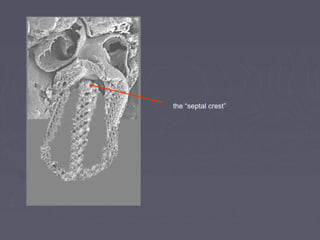

►   The medial walls of the expanding

ventricles become apposed and

gradually merge, forming the

muscular interventricular septum

the “septal crest”

lumen of the original tube,

here.

It forms a communication

between the ventricles: persistence of

it will result in the commonest

of ventricular septal defects, the

perimembraneous VSD